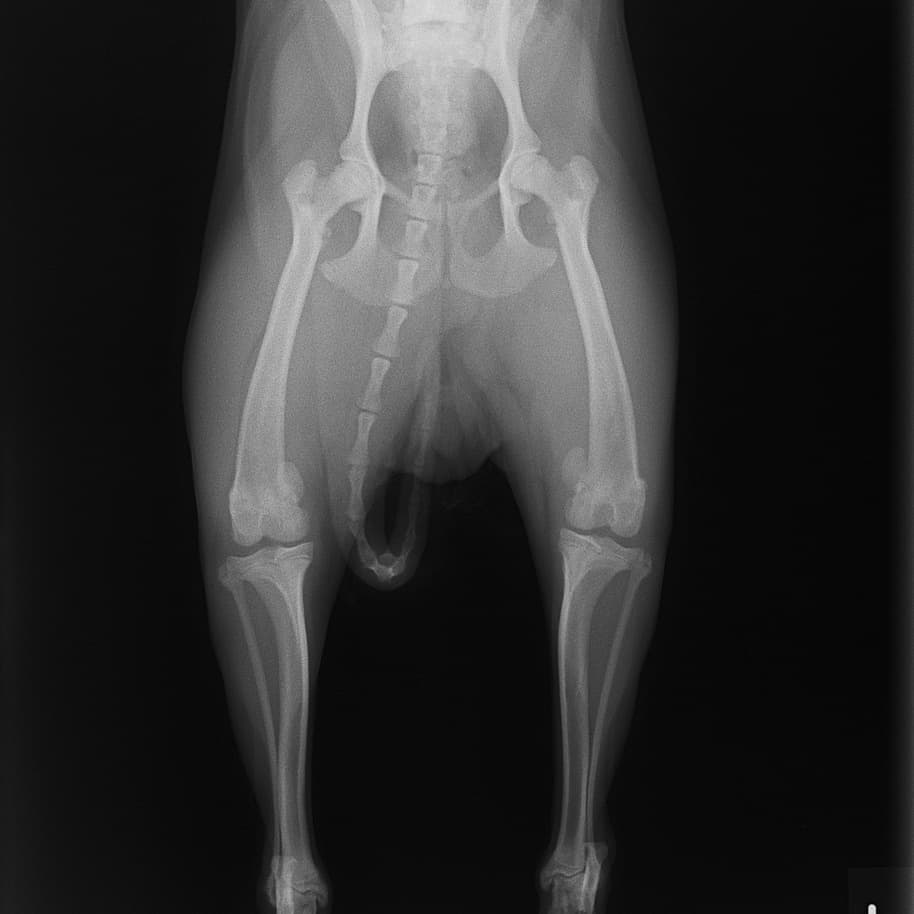

■ 症例24 キャバリア 7か月

左右膝蓋骨内方脱臼(左:グレードⅣ 右:グレードⅢ)

以前から左右後肢の跛行が認められ、整形外科学的検査・レントゲン検査により左右の膝蓋骨脱臼が認められた。症状が重度である左膝の膝蓋骨脱臼整復術を行った。外科手技は縫工筋及び内側広筋の解放、脛骨粗面の外側転位、滑車ブロック形造溝術、内外側関節方の縫縮を実施した。術後一か月時点で、左の膝蓋骨は安定しており経過は良好である。

本症例は成長期における重度の膝蓋骨脱臼であり、術後の再発の可能性もあるため、経過をしっかりと観察していく必要がある。また、今回手術を実施していない右膝に関しても経過を観察し、手術を検討していくこととする。